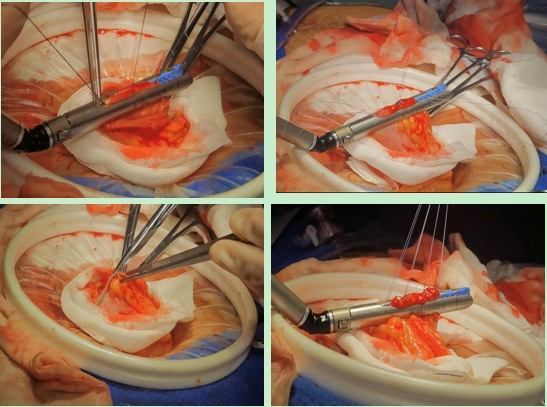

我院外科二病区主治医师亢浩文进修回院后,经过反复的琢磨与模拟操作,近日将传统的肠道手术吻合方式精进为三角吻合,即利用三角形稳固原理,使用三个钉仓分别闭合两断端肠管后壁、侧壁、前壁。这样不仅保留了原有生理解剖结构及顺序,减少了吻合口张力,并且术中可直视观察吻合口是否出血,进而降低吻合口并发症的发生。该吻合方式尤其适用于回肠-结肠、结肠-结肠吻合中的消化道重建,且患者术后排气排便时间明显缩短,2-3天即可恢复肠功能。目前,我院已采用三角吻合技术成功完成3例手术,均取得了满意的治疗效果。